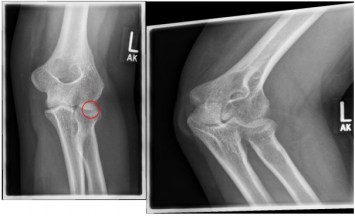

Ellenbogen2

Photo: A fracture with several framents